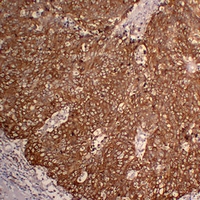

• Immunohistochemical analysis of Cytokeratin 5 staining in human cervical squamous carcinoma formalin fixed paraffin embedded tissue section. The section was pre-treated using heat mediated antigen retrieval with sodium citrate buffer (pH 6.0). The section was then incubated with the antibody at room temperature and detected using an HRP conjugated compact polymer system. DAB was used as the chromogen. The section was then counterstained with haematoxylin and mounted with DPX.

• Immunohistochemical analysis of Cytokeratin 5 staining in human squamous cell lung carcinoma formalin fixed paraffin embedded tissue section. The section was pre-treated using heat mediated antigen retrieval with sodium citrate buffer (pH 6.0). The section was then incubated with the antibody at room temperature and detected using an HRP conjugated compact polymer system. DAB was used as the chromogen. The section was then counterstained with haematoxylin and mounted with DPX.

• Immunohistochemical analysis of Cytokeratin 5 staining in human lung squamous cell carcinoma formalin fixed paraffin embedded tissue section. The section was pre-treated using heat mediated antigen retrieval with sodium citrate buffer (pH 6.0). The section was then incubated with the antibody at room temperature and detected using an HRP conjugated compact polymer system. DAB was used as the chromogen. The section was then counterstained with haematoxylin and mounted with DPX.

• Immunohistochemical analysis of Cytokeratin 5 staining in human skin squamous cell carcinoma formalin fixed paraffin embedded tissue section. The section was pre-treated using heat mediated antigen retrieval with sodium citrate buffer (pH 6.0). The section was then incubated with the antibody at room temperature and detected using an HRP conjugated compact polymer system. DAB was used as the chromogen. The section was then counterstained with haematoxylin and mounted with DPX.

• Immunohistochemical analysis of Cytokeratin 5 staining in human tonsil formalin fixed paraffin embedded tissue section. The section was pre-treated using heat mediated antigen retrieval with sodium citrate buffer (pH 6.0). The section was then incubated with the antibody at room temperature and detected using an HRP conjugated compact polymer system. DAB was used as the chromogen. The section was then counterstained with haematoxylin and mounted with DPX.